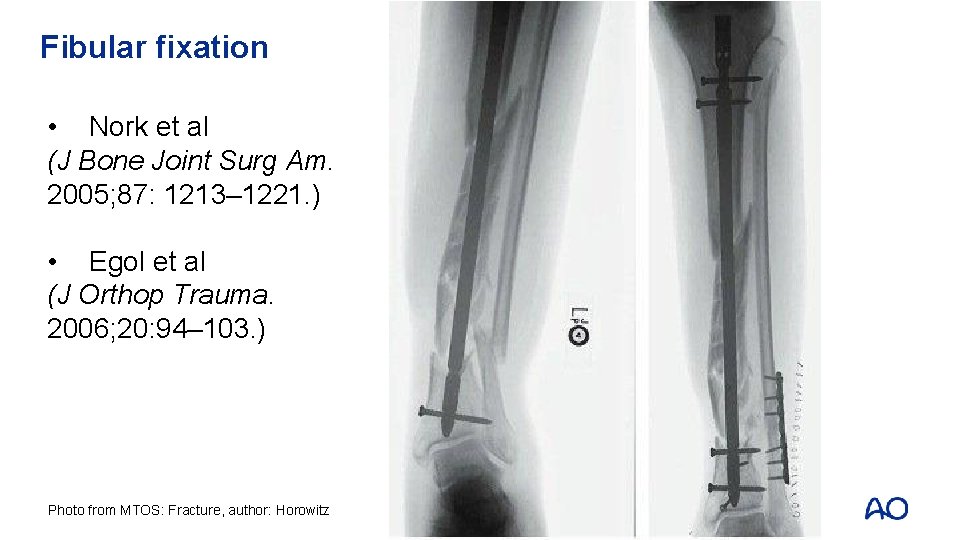

Reduction aids for distal fractures • Pointed (percutaneous) clamps • External fixation • Steinman pin • Fibular fixation • Blocking screws

Fibular fixation • Nork et al (J Bone Joint Surg Am. 2005; 87: 1213– 1221. ) • Egol et al (J Orthop Trauma. 2006; 20: 94– 103. ) Photo from MTOS: Fracture, author: Horowitz